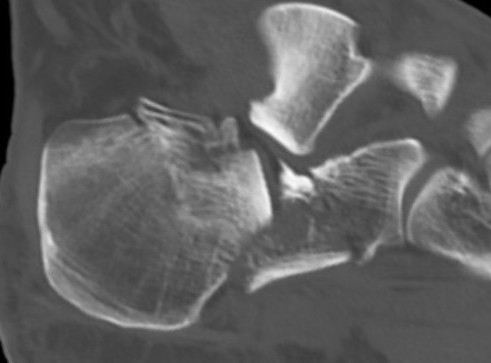

CT scan

| Coronal | Sagittal | Axial |

|---|---|---|

|

Posterior facet / number of fragments Sustenaculum tali Heel widening |

Bohlers angle Posterior facet depression / angulation |

Calcaneocuboid joint Sustenaculum tali |